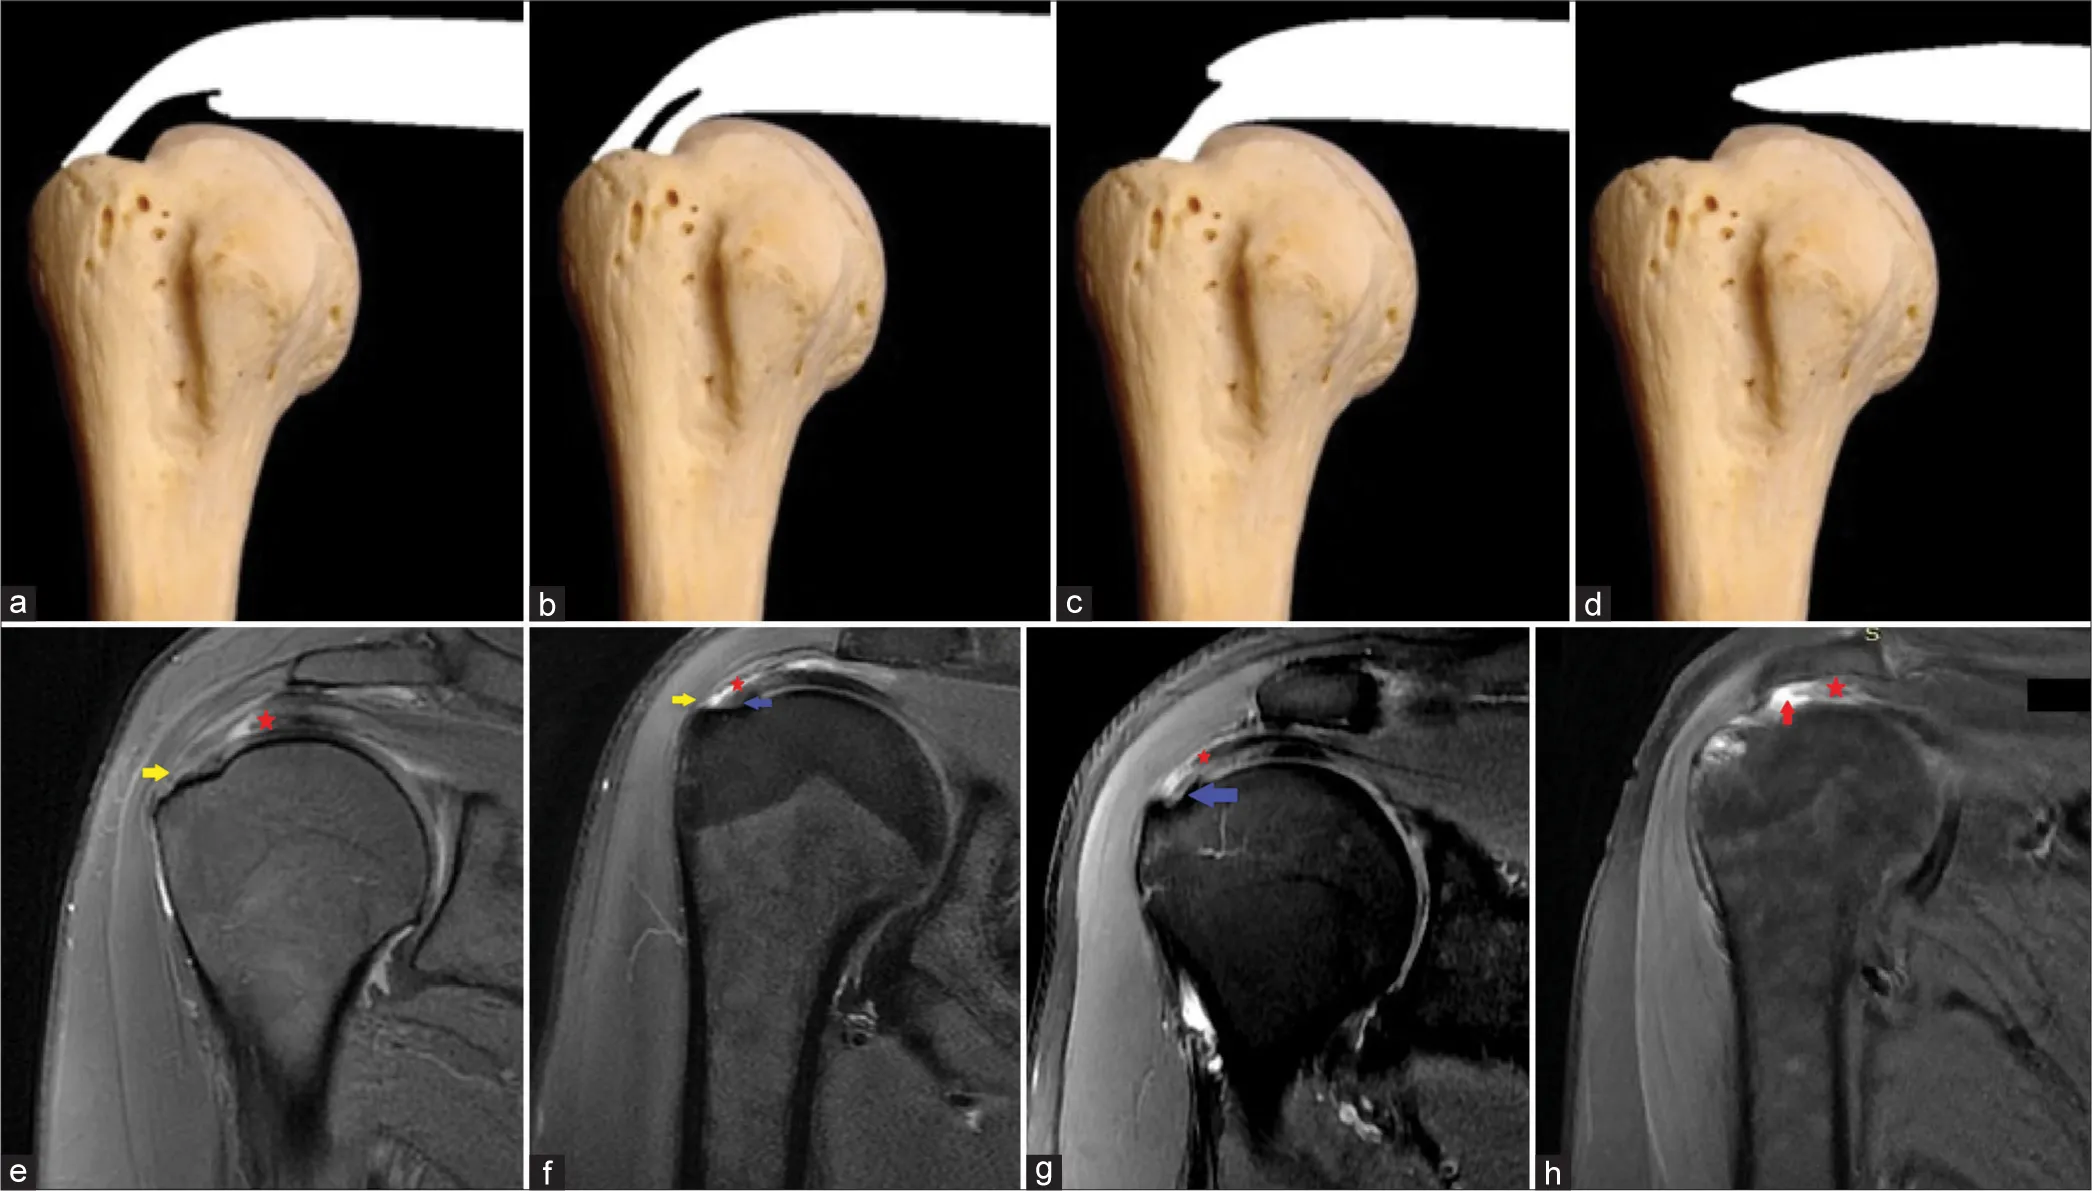

Types of Rotator Cuff Tears

• Partial Tear – The tendon is damaged but not completely detached from the bone.

• Complete Tear – The tendon is fully separated from the bone, often requiring surgical repair.